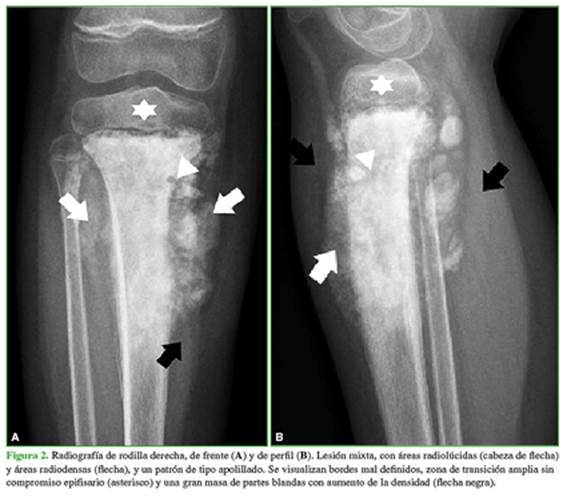

En las radiografías de la rodilla derecha (Figura 2), se visualiza una lesión de aspecto mixto, con un patrón de tipo apolillado, áreas radiolúcidas y áreas radiodensas, localizada en el extremo proximal de la tibia, en el sector metafisodiafisario. Hay un importante compromiso perióstico y aumento de la densidad de partes blandas. Se observa una zona de transición amplia, con bordes mal definidos. Impresiona que no hay compromiso epifisario.